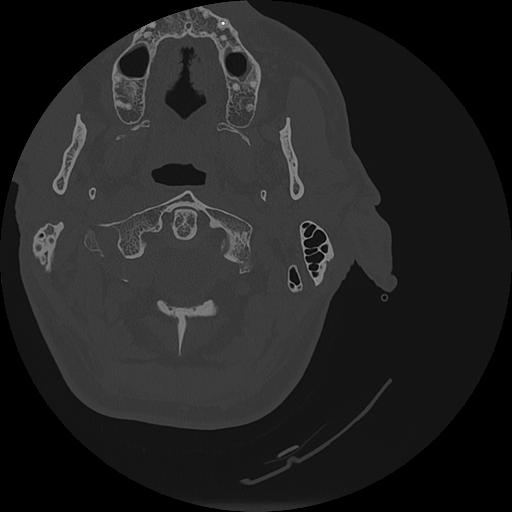

7 HUESO,,Vol,0.5,HUESO,,